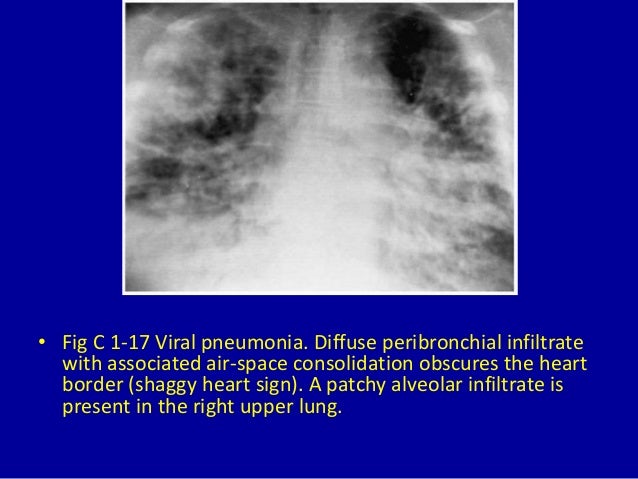

Shaggy Heart Sign